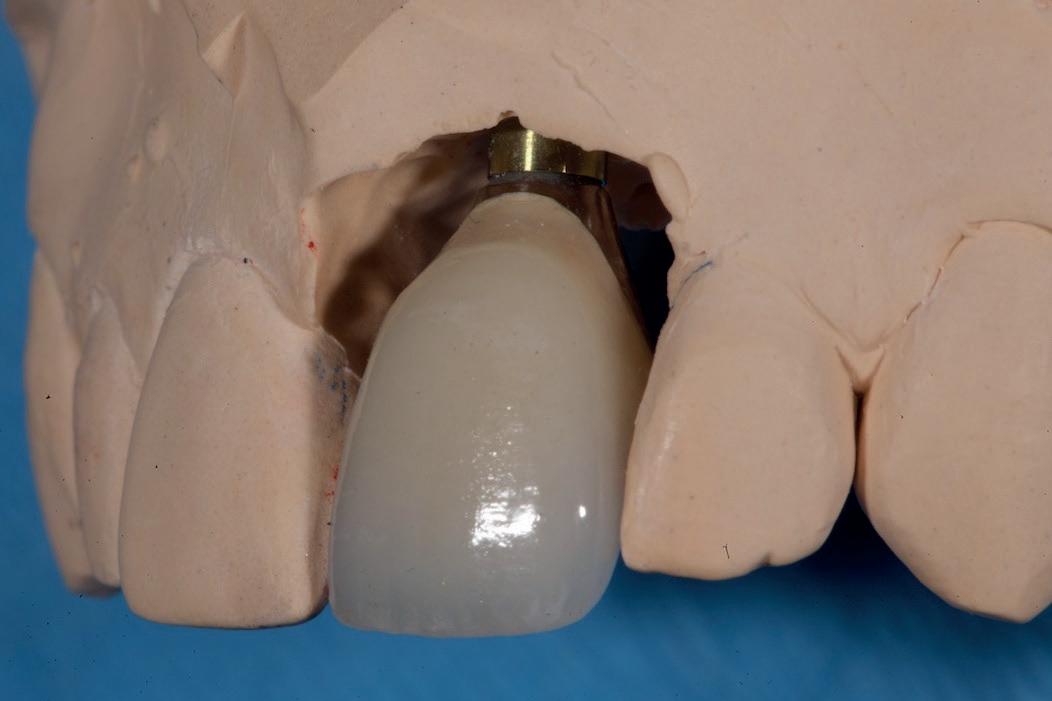

SITE AUGMENTATION Reconstituirea țesutului moale periimplantar și papilar în zona estetică

RECONSTITUIREA țesuturilor moi periimplantare. Scopul acestui raport de caz este de a demonstra procedurile chirurgicale utilizate pentru corectarea unui defect al țesuturilor moi periimplantare folosind țesutul moale interdentar în combinație cu tuberozitatea ca locație donatoare de țesut conjunctiv, utilizând o abordare prin tunelizare într-o zonă estetică.